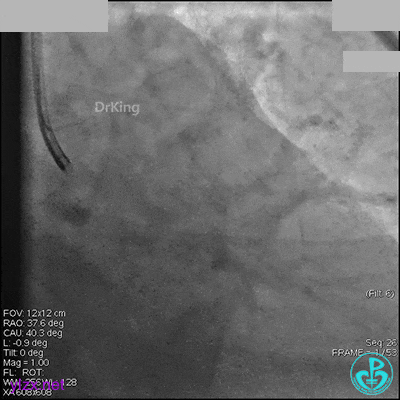

右冠脉中段充分扩张后欲植入3.5×38mm支架时,支架难以通过中远段扭曲处,且指引导管、导丝弹出飞扬。反复尝试导丝重新到达右冠脉远端时通过不顺利,局部造影剂滞留,远端血流接近3级。

右冠脉血流3级,患者无症状,终止手术。

术后患者无特殊不适。

1周后再次上台,右冠脉3级血流,3段局限性严重狭窄,内膜模糊,应该是上次操作夹层遗留下的血肿。